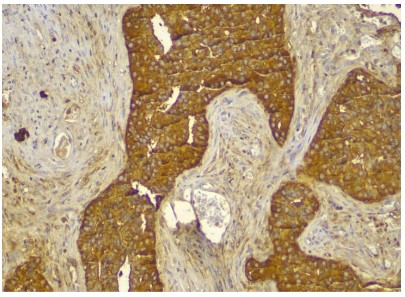

The gross cystic mass measures 10 x 7 x 5 cms, external surface was bosselated irregular with congestion, the normal pancreatic tissue was pushed to the periphery. The cyst was sectioned to reveal tan and red variegated cystic and solid cut surfaces. Microscopic examination demonstrated cystic wall lined by glycogen rich clear cells arranged in a single cuboidal layer without mucin. The Linning epithelial cells demonstrate high grade of dysplasia and foci of microinvasive adenocarcinoma. Perineural and lymphovascular invasion were not identfied. Immunohistochemistry was performed for further confirmation which showed CK-7, CK- 19, CA19.9 positive while CK-20, CDX-2, CEA were negative thus diagnosis of serous cystadenocarcinoma was confirmed.

Figure 6 & 7: CK-7 Positive (top). CK-19 Positive (bottom).

Figure 8: CA 19-9 Positive.